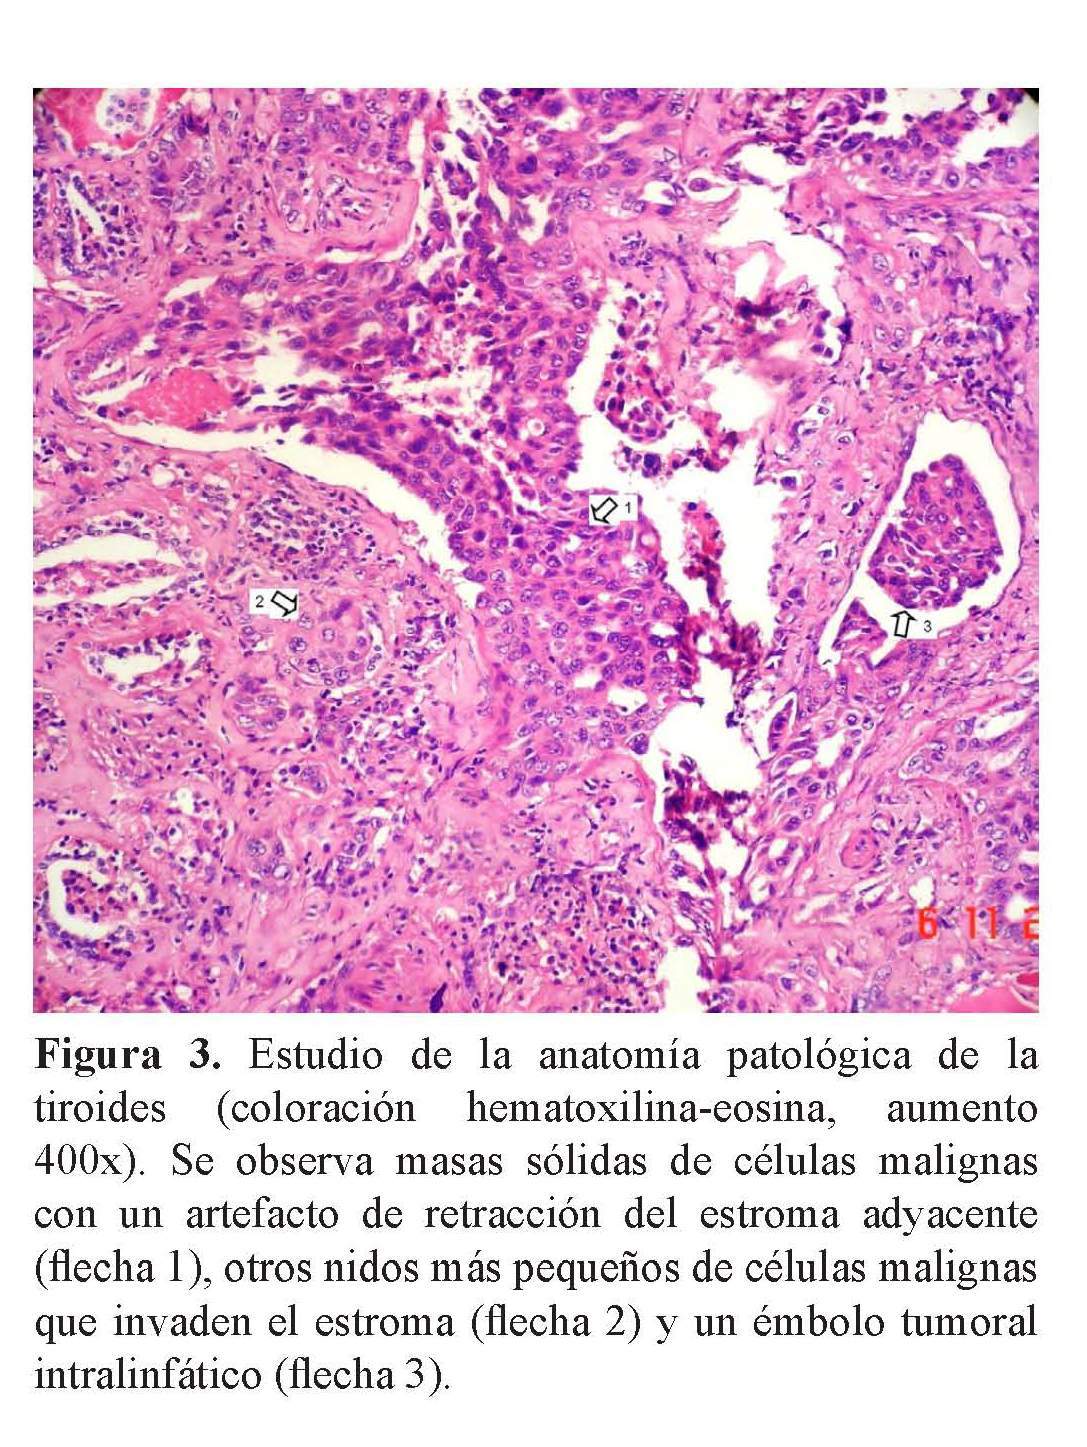

V Congreso Virtual Hispanoamericano de Anatomía Patológica CARCINOMA